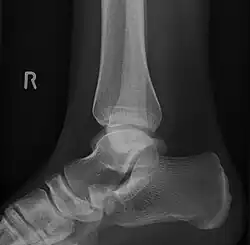

Radiological images

Lateral projection of type 2 -